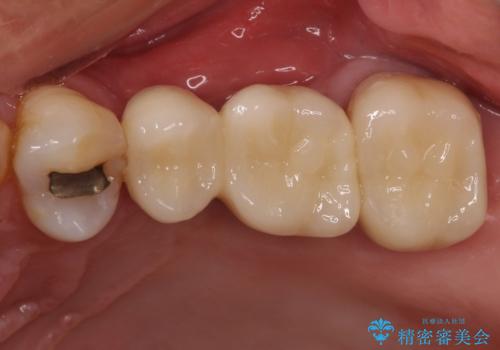

部分矯正を併用した奥歯のインプラント補綴治療

部分矯正期間中はアンカースクリューやフック、ゴムなどが粘膜にあたり、大変な思いをすることになりましたが、そのおかげでインプラント補綴した歯と最後方歯の位置が非常に良好となり、まるでご自身の歯のように咬むことができるようになりました。